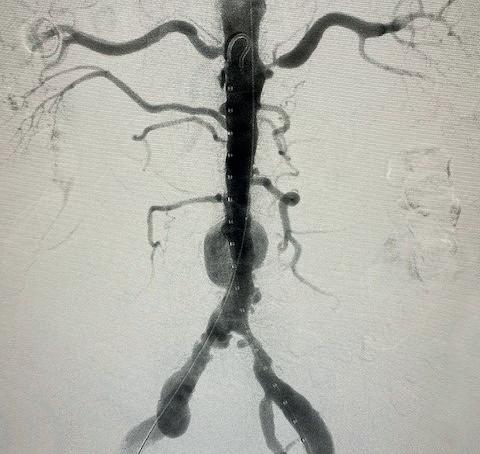

We used a percutaneous approach. Initially, we were unable to advance the 16Fr DrySeal sheath for the main graft on the right or the 12Fr DrySeal sheath on the left side for the contralateral limb (Figure 3). At this point, we performed IVL with a 7.0x60mm IVL catheter, of both the right and left common iliac arteries. We delivered 150 pulses to each vessel at 4atm and subsequently carefully dilated to nominal pressure of 6atm. Both arteries dilated easily. The Gore Excluder graft was delivered, and the limbs were placed within the common iliac arteries. Post-implantation balloon angioplasty was completed and revealed complete seal of the AAA and no residual stenosis in the iliacs (Figure 4). The patient was found to have a 90% stenosis of the left renal artery, which was treated with a balloon-expandable stent. His postprocedural CT scan revealed a very nice result, a sealed AAA, wide iliac arteries, and no residual stenosis.

Figure 4. Completion arteriogram, areas of stenosis completely resolved